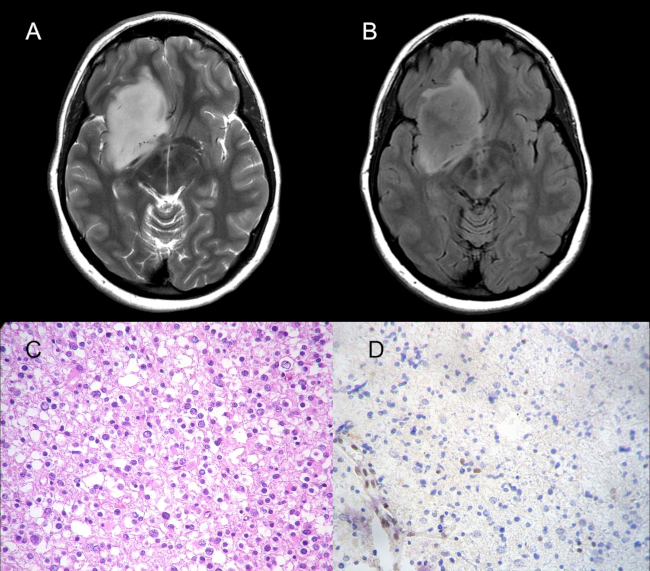

El resultado de la neuropatología del único paciente codelecionado con presencia del signo del mismatch (falso positivo) de nuestra cohorte, presentó adicionalmente a la codeleción 1p/19q, mutación del gen p53, deleción del gen 10q, y el estudio por inmunohistoquimica del ATRX evidenció su inactivación (►Fig. 4). Esos hallazgos sugieren el diagnóstico de un probable glioma mixto.

En nuestro estudio, documentamos un único paciente con diagnóstico histológico de oligodendroglioma y presencia de la codeleción 1p/19q que presentaba el signo del mismatch (►Fig. 4). Por consiguiente, y a diferencia de las publicaciones anteriormente mencionadas que han reportado un VPP de 100%, obtuvimos un VPP de 93,8% para predecir la ausencia de codeleción. En el conocimiento de los autores, este trabajo representa una de las pocas publicaciones a nivel mundial en demostrar falsos positivos relacionados al signo del mismatch. El primer reporte fue publicado por Juratli y col,11 quienes evaluaron el signo en 133 pacientes sobre una cohorte de gliomas grado II y III IDH mutados y no mutados, detectando mismatch T2-FLAIR en 28% y 29,5% de gliomas IDH-mutados, 1p/ 19q codelecionados grado II y grado III respectivamente. Lee y col.,12 reportaron también valores predictivos inferiores al 100% en un estudio donde obtuvieron 10 falsos positivos. Asimismo, Johnson y col.13 han publicado un reporte de casos donde identificaron el signo en pacientes que no cumplían de forma conjunta la mutación del IDH y la ausencia de la codeleción 1p/ 19q. En su reporte, exponen un paciente con diagnóstico de oligodendroglioma molecularmente definido que presenta el signo del mismatch.

Tal como se comentó previamente, el único falso positivo de nuestro estudio (presencia de signo del mismatch T2-FLAIR y de la codeleción 1p/19q) demostró ciertas particularidades en los resultados del análisis de la biología molecular. El estudio para la detección de mutaciones del gen p53 demostró una duplicación en los codones 241 S y 242 C del exón 7. Por otro lado, se detectó también la deleción del gen 10q. El estudio por inmunohistoquimica del ATRX evidenció su inactivación. Es de nuestro interés destacar esos hallazgos, ya que esas alteraciones genéticas como las mutaciones en el gen p53 no son características habituales de los oligodendrogliomas, más bien son alteraciones genéticas típicamente vinculadas a los astrocitomas. Como se comentó previamente y se expone en la bibliografía, la mutación del p53, al igual que la inactivación del ATRX, son mutuamente excluyentes con la codeleción 1p/19q. Esa incongruencia sugiere el diagnóstico de un glioma mixto, diagnóstico desaconsejado en la última clasificación dado que, con el estudio molecular, la mayoría son finalmente compatibles con oligodendrogliomas al estar codelecionados o astrocitomas en caso contrario.1